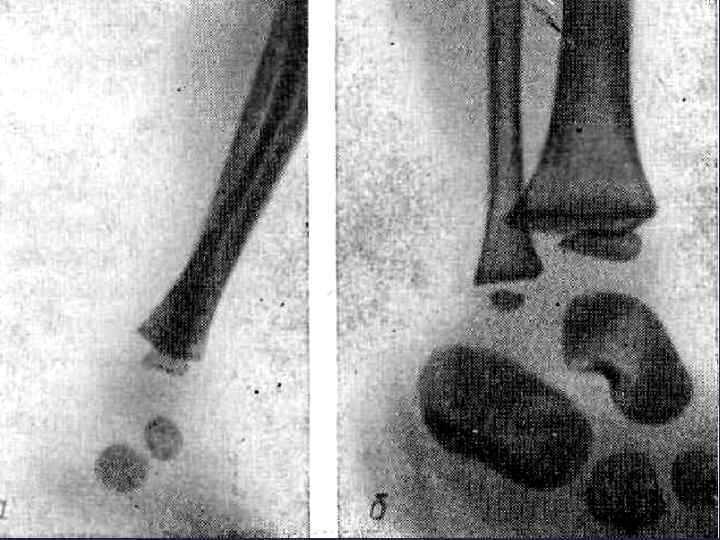

ГОЛЕНОСТОПНЫЙ СУСТАВ И СТОПА - т. о в пяточной кости - 6 мес внутриутробно - т. о. в таранной к. - 7 -8 мес в-у - т. о. в кубовидной к. - 9 мес в-у - т. о в лат. клиновидной - 1 год - т. о. в дистал. эпифизе б/берцовой к. - 2 года (синостоз 16 -19) лет - т. о в дистал. эпифизе м/берц. кости -2 -3 года (син. - 2022 года) - т. о. в истинных эпифизах коротких трубчатых костей -2 -3 года ( син. - 20 -25 лет) - т. о в медиал. клиновидной кости - 2 -4 года - т. о. в промежут. клин. к. - 3 -4 года - т. о. в ладьевидной к. - 4 -5 лет - несколько т. о в апофизе пяточной кости ( бугор) - 7 -9 лет, синостозирование пяточной кости - 12 -15 лет.

ГОЛЕНОСТОПНЫЙ СУСТАВ И СТОПА - т. о в пяточной кости - 6 мес внутриутробно - т. о. в таранной к. - 7 -8 мес в-у - т. о. в кубовидной к. - 9 мес в-у - т. о в лат. клиновидной - 1 год - т. о. в дистал. эпифизе б/берцовой к. - 2 года (синостоз 16 -19) лет - т. о в дистал. эпифизе м/берц. кости -2 -3 года (син. - 2022 года) - т. о. в истинных эпифизах коротких трубчатых костей -2 -3 года ( син. - 20 -25 лет) - т. о в медиал. клиновидной кости - 2 -4 года - т. о. в промежут. клин. к. - 3 -4 года - т. о. в ладьевидной к. - 4 -5 лет - несколько т. о в апофизе пяточной кости ( бугор) - 7 -9 лет, синостозирование пяточной кости - 12 -15 лет.